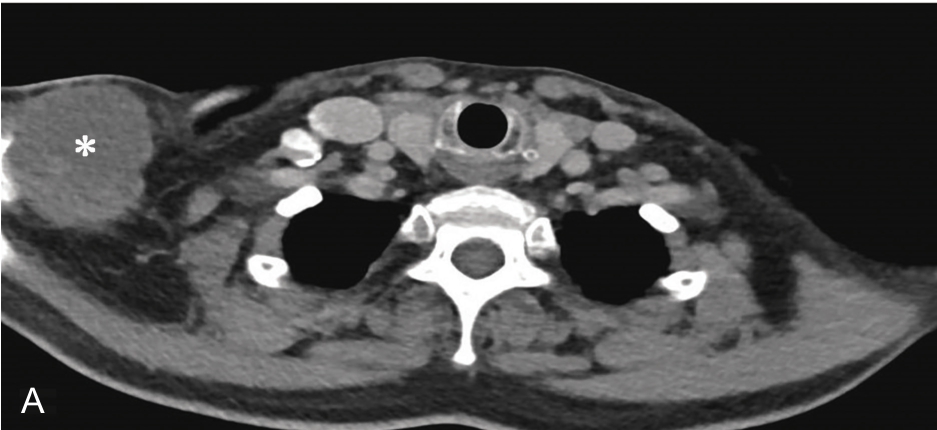

▲ 图2-1-12 超声引导下右侧肩关节周围滑膜囊肿穿刺治疗

A~B.患者肩关节MRI,星号及测量键:滑膜囊肿